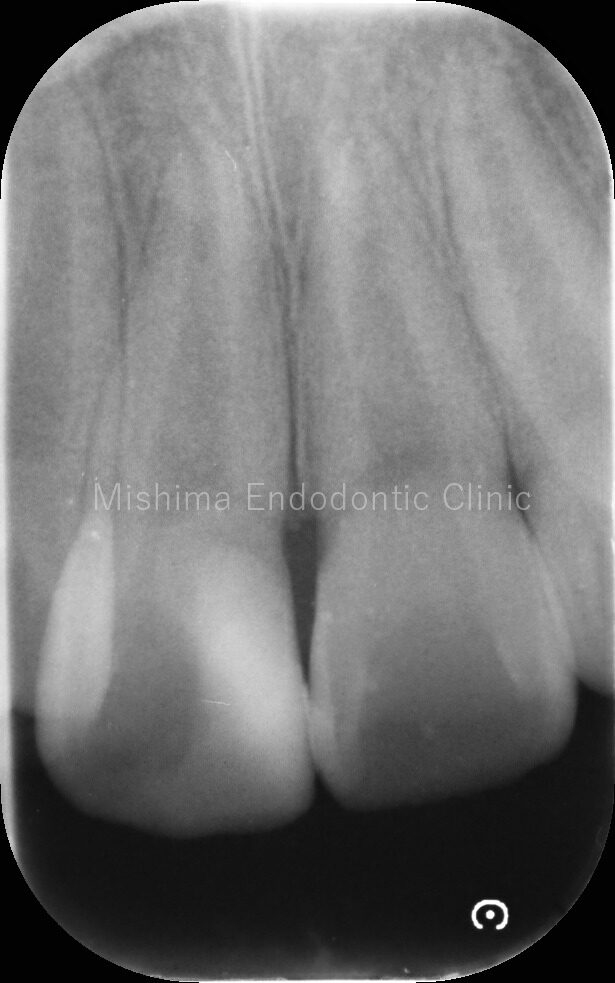

術前

レントゲン